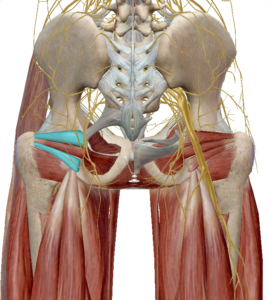

(5) 쌍자근

쌍자근은 고관절의 심부 외회전근육으로 상쌍자근과 하쌍자근이 존재합니다.

좌골에서 대퇴골 후면으로 이어져 고관절의 외회전 기능을 발생합니다.

(6) 대퇴방형근

대퇴방형근은 좌골과 대퇴골을 연결하는 근육으로

수축 시 고관절의 외회전을 발생합니다.